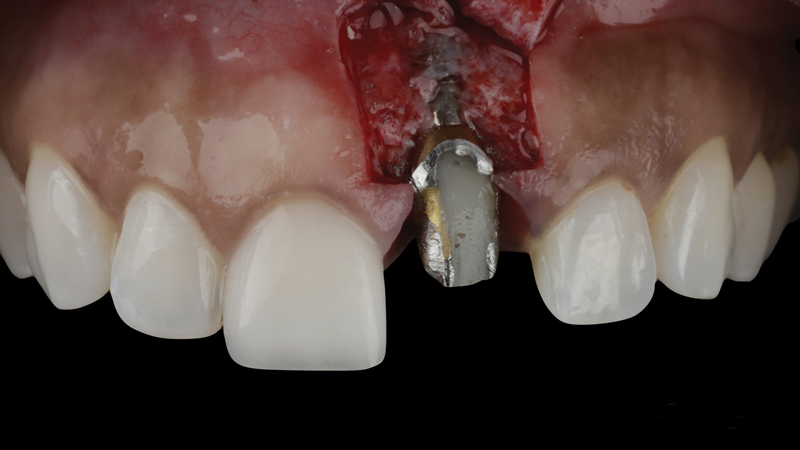

(3.) The crown was removed, and a partial thickness flap was reflected using a papilla-sparing incision design, which revealed that the implant was positioned too far facially and that its body was visible through a very thin layer of bone.

Figure 3

The patient in this case had undergone implant therapy at the site of tooth No. 9 and was restored with a cement-retained restoration more than 5 years prior. At presentation, the site demonstrated a peri-implant soft-tissue dehiscence that extended approximately 3-mm apical to the gingival margin of tooth No. 8. Thin and erythematous marginal tissue was evident at the zenith (Figure 2). The crown was removed, and a partial thickness flap was reflected using a papilla-sparing incision design. This revealed that the implant was positioned too far facially and that its body was visible through a very thin layer of bone (Figure 3 and Figure 4). The first objective of treatment was to minimize the facial extent of the emerging abutment and crown. To accomplish this, the facially positioned abutment and implant crown margin were both recontoured. The second treatment objective was to provide additional supracrestal soft tissue that would more adequately maintain the peri-implant margin. The tuberosity was selected as a donor site due to its dense, high-quality connective tissue, low propensity for shrinkage, and association with minimal patient discomfort. Once the graft was secured (Figure 5 through Figure 7), the flap was coronally positioned (Figure 8). After a healing period of 2 weeks, the margin of tooth No. 9 exhibited an ideal position in relation to its contralateral counterpart and demonstrated increased soft tissue thickness (Figure 9). Three months postoperatively, further healing had improved the esthetics and the position of the margin had been maintained (Figure 10).